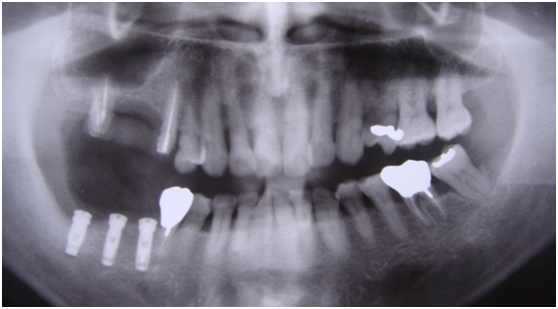

97/09/18 拔牙半年後安排右下第一小臼齒植牙前

97/09/23 右下第一小臼齒植牙完成時

98/01/08經過三個半月做右下第一小臼齒的二階暴露,發覺鄰牙的植體高度竟已掉下來

980305幫患者補角化牙齦並翻開清除發炎組織,期待能阻止繼續骨破壞

期間患者偶爾出血但並無明顯不適

直到經過一年半後,於99/07/19又有明顯發炎,拍攝追蹤片,發覺連同更遠心的那顆植體的骨頭也破壞下降了

99/07/19